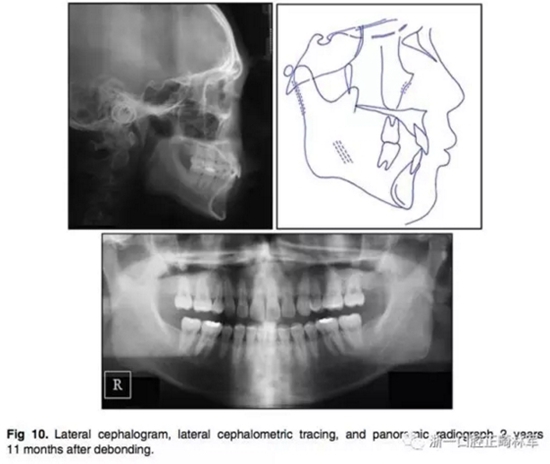

3.在2年11個月后,患者回來復(fù)診,他的面部形態(tài)仍然可以接受,但是他的唇部厚度顯著增加,結(jié)果,他的唇部已經(jīng)變得略微突出(Fig 9、Fig10)。他的咬合仍然穩(wěn)定,但他的咬合力略有增加。切牙區(qū)出現(xiàn)了間隙。

4.頭顱測量疊加顯示有一定的下頜頜骨生長。矢狀面骨關(guān)系穩(wěn)定(ANB由4.4為4.1°),下頜平面逆時針旋轉(zhuǎn)(Fig 11)。